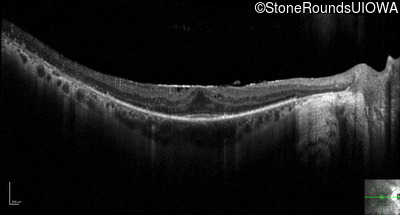

Optical Coherence Tomography - Right - 20/25 -3

Exemplar / OCT Stack

OCT Stack